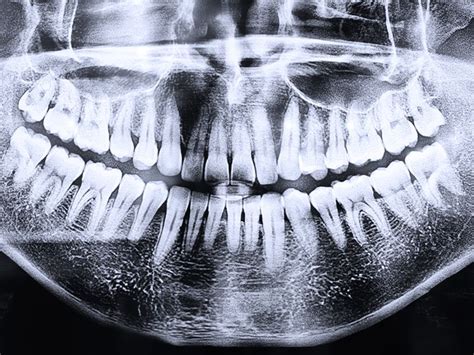

El segundo paso a seguir es hacerte una radiografía panorámica para dar un mejor diagnóstico. Después de realizarte la radiografía panorámica nuestros especialistas te harán una exploración minuciosa del estado de tu salud bucodental y poder proponer el mejor plan de tratamiento a tus necesidades. En nuestra clínica dental en Rivas, realizamos un estudio minucioso y exhaustivo para poder aplicar el tratamiento correspondiente.